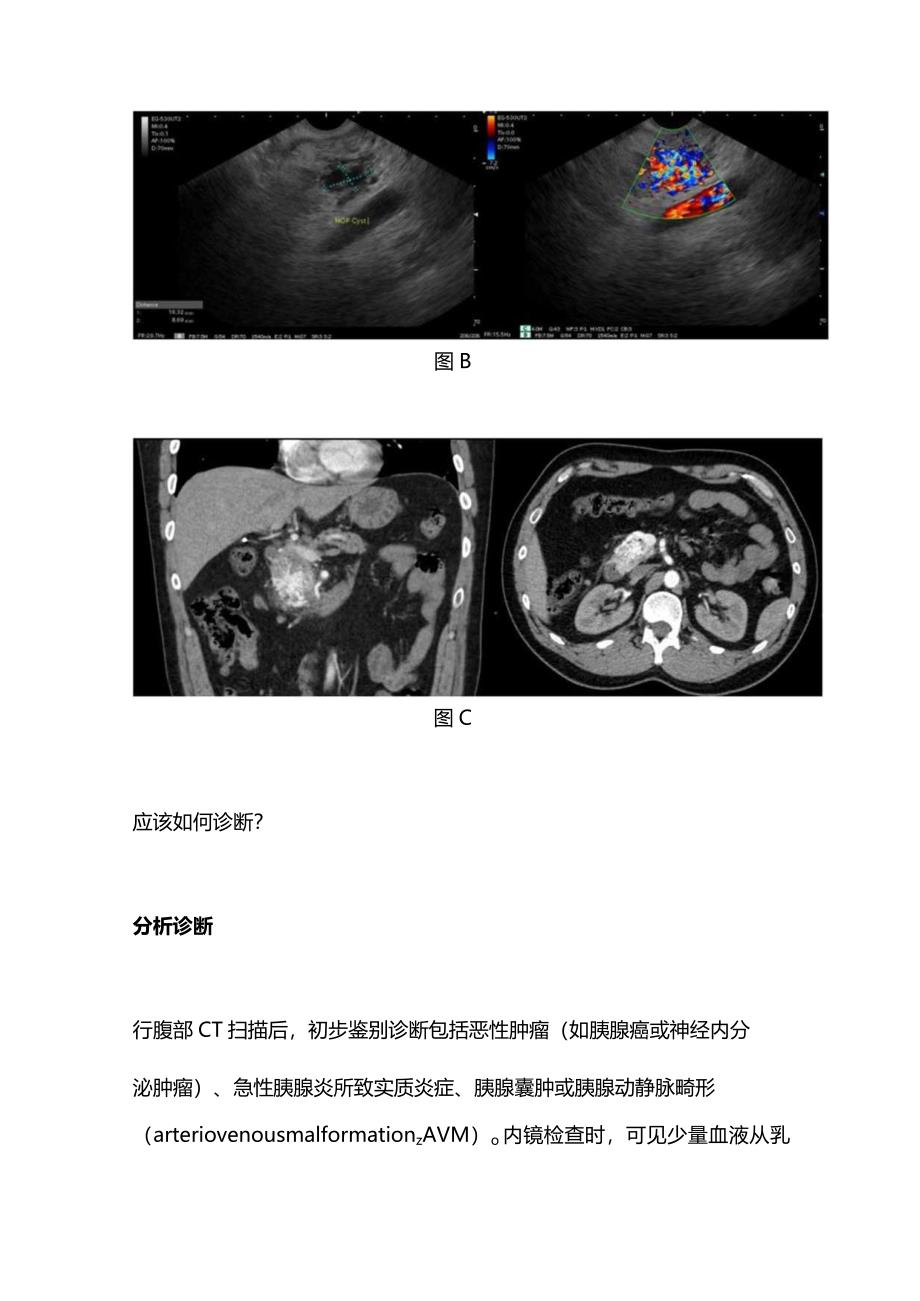

2、管造影如图C所示。图B图C应该如何诊断?分析诊断行腹部CT扫描后,初步鉴别诊断包括恶性肿瘤(如胰腺癌或神经内分泌肿瘤)、急性胰腺炎所致实质炎症、胰腺囊肿或胰腺动静脉畸形(arteriovenousmalformationzAVM)o内镜检查时,可见少量血液从乳头部流出(即胰管出血)(图A)。EUS(图B)显示胰头部有-16mm9mm的肿块,彩色多普勒超声显示动脉和静脉波形,提示可能为AVMo行CT血管造影(图C),证实为胰头AVMo随后,介入放射学团队进行血管造影,证实为胰腺AVM。结合胰腺炎最初表现和胰管出血现象,本例患者因胰腺AVM出血流入胰管,导致胰管阻塞,从而引发急性胰腺炎。诊断结果: